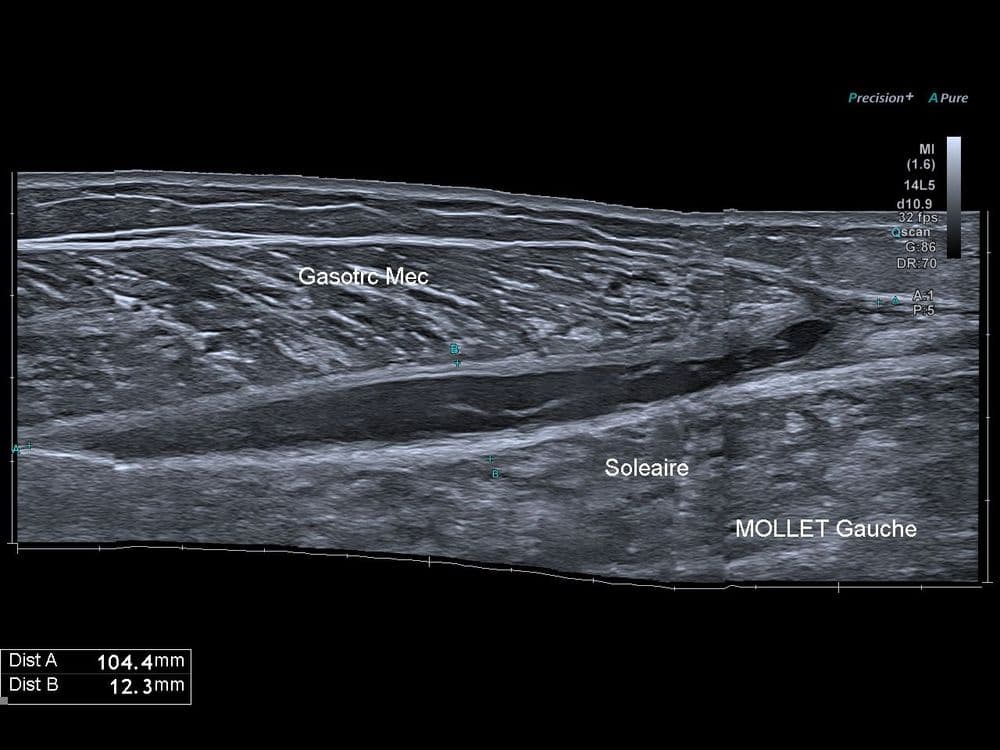

Evolution cicatricielle d'un tennis leg

Suivi échographique pendant 3 mois de l'évolution d'un tennis leg.